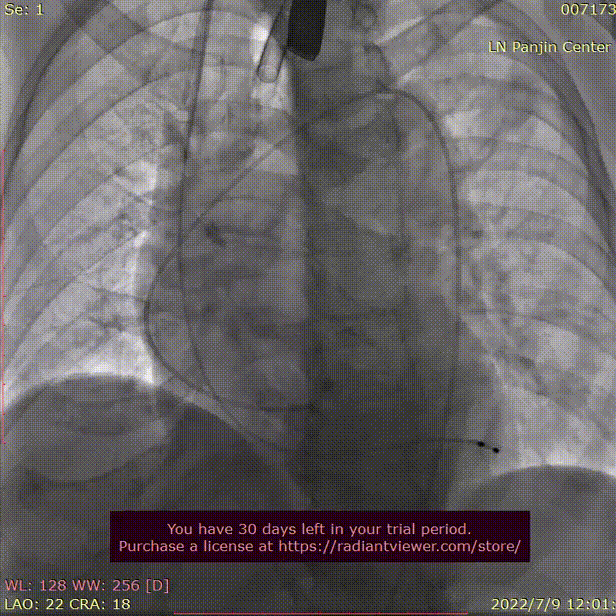

弓部及入路评估

入路血管: 双侧股髂动脉轻度扭曲,髂动脉分叉前后钙化严重,双侧股动脉穿刺位点均有钙化,左侧偏轻;右侧入路血管直径偏细,左侧尚可。